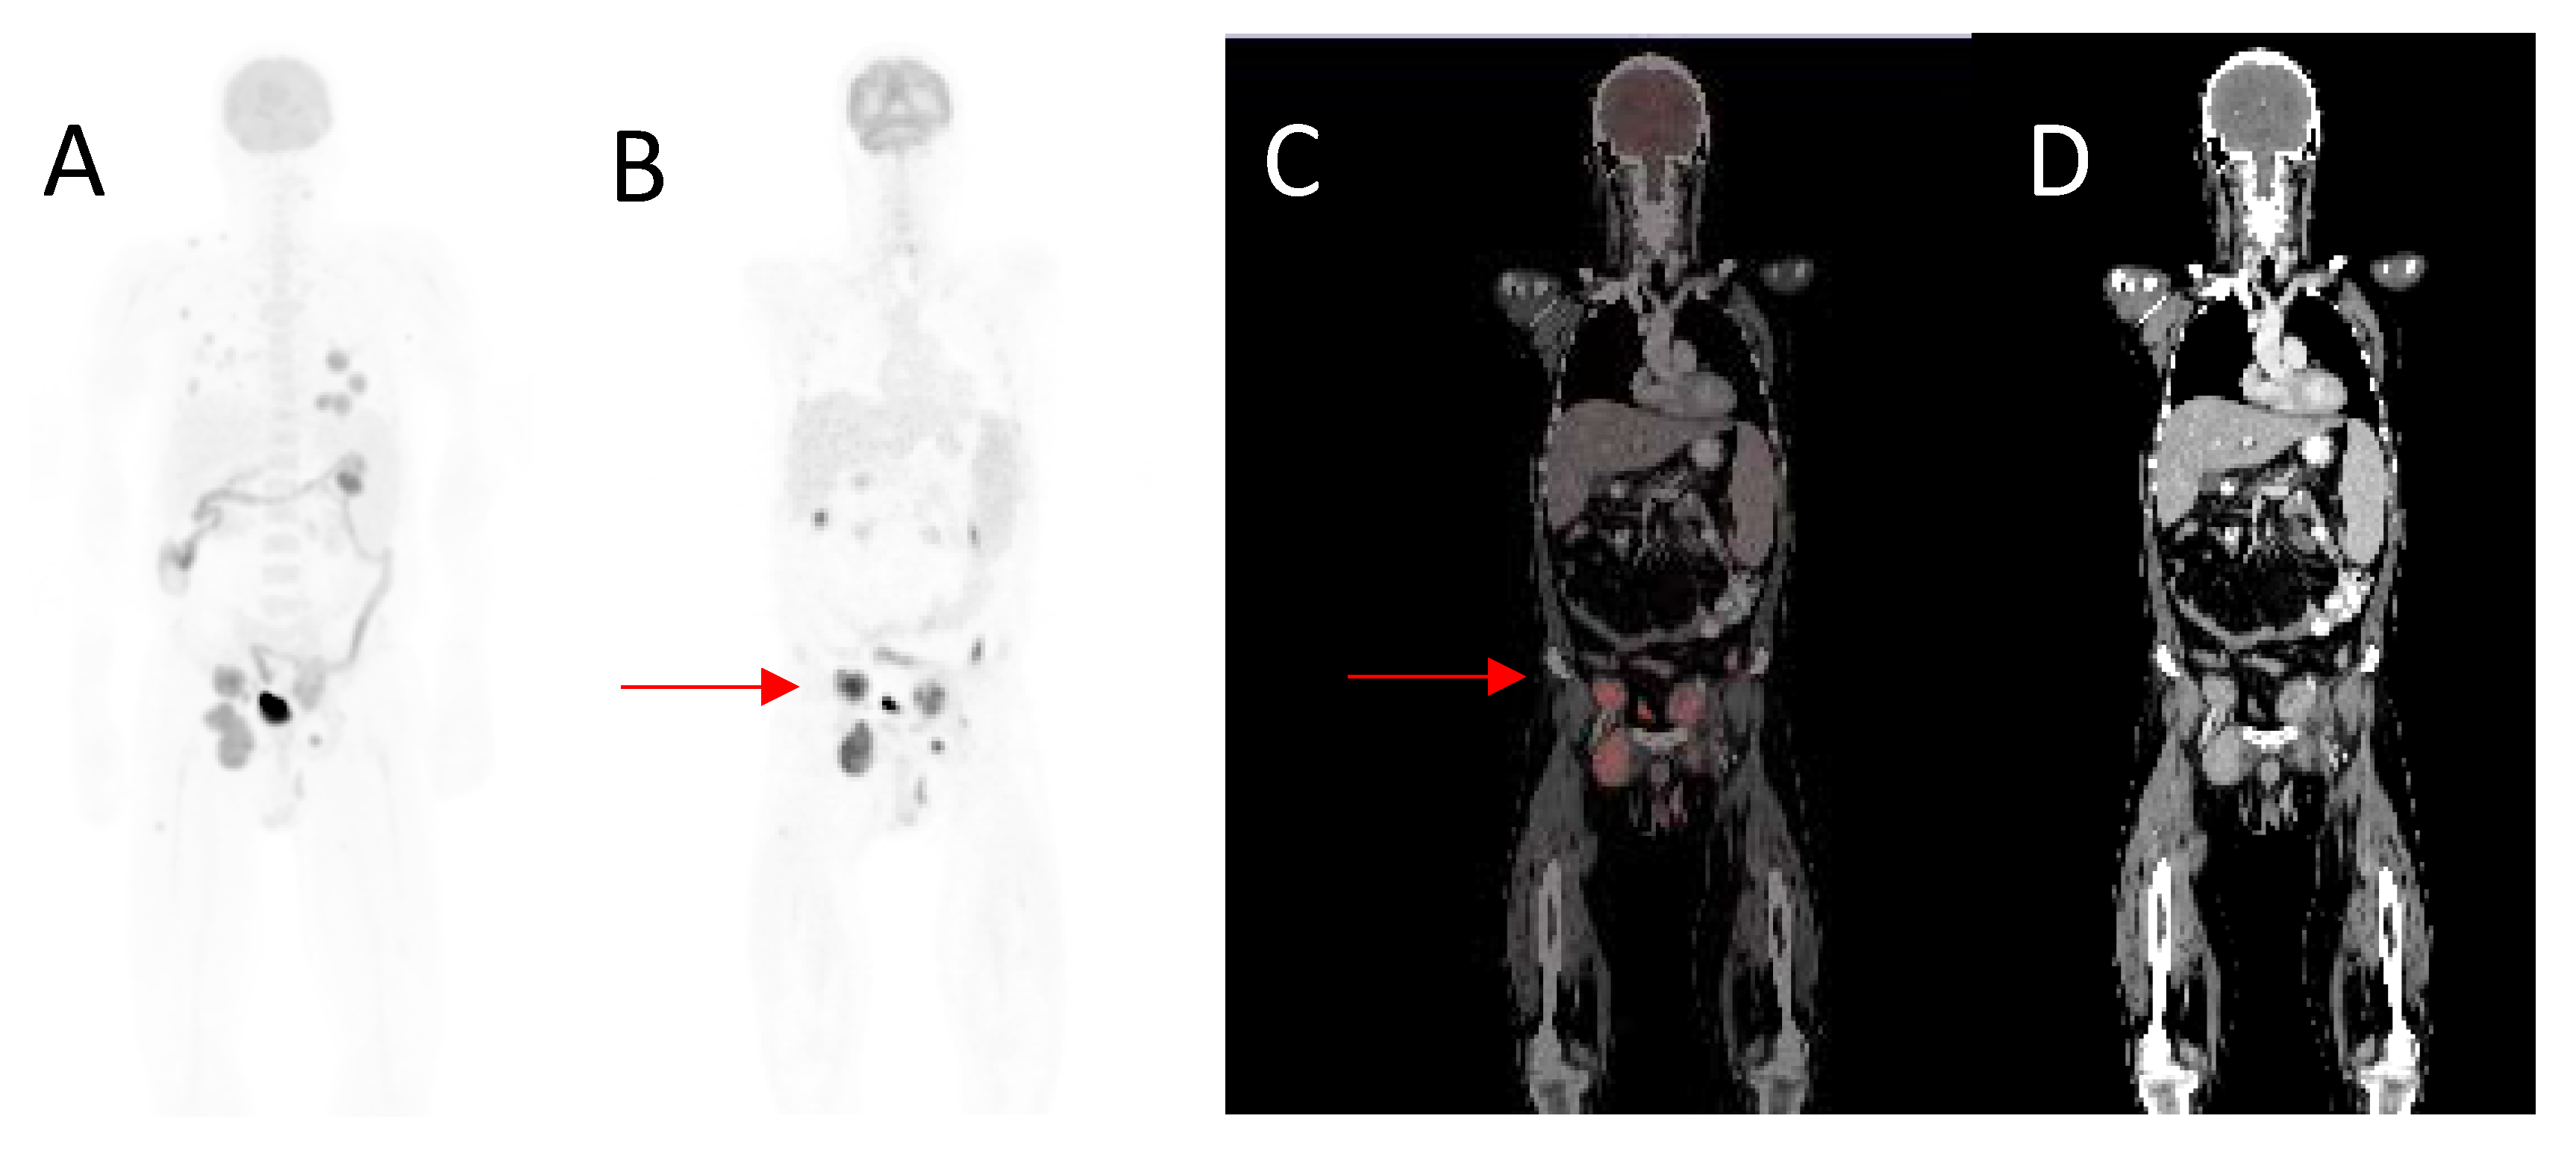

Figure 3.

A 50-year-old male, diagnosed with malignant melanoma of the right groin with inguinal lymph node metastases, excision and resection of metastatic inguinal nodes, presented with right groin recurrence. Maximal intensity projection image (A), coronal 18F-FDG- PET (B), fused (C) and CT (D) images demonstrating right inguinal recurrence (arrow). He also had abdominal and retroperitoneal lesions. MTV 174.59 cm3, TLG 1611.46, SUVmax 22.12, whole-body MTV 780.55 cm3 and whole-body TLG 28,279.33. Overall survival was 5 months.